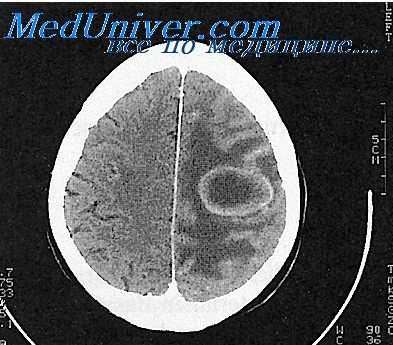

Решающим для подтверждения диагноза менингита является исследование цереброспинальной жидкости. По показаниям проводят дополнительные исследования (рентгенографию черепа и придаточных пазух носа, осмотр глазного дна, электроэнцелографию, эхо-энцефалографию, компьютерную и ядерно-магнитнорезонансную томографию). При люмбальной пункции определяют давление цереброспинальной жидкости, проводят ликвородинамические пробы Стуккея и Квикенштедта, определяют визуальные характеристики жидкости (прозрачность, цвет). В осадке жидкости определяют количество и состав клеток, наличие микрофлоры. Проводят биохимические (количество белка, глюкозы, хлоридов, осадочные пробы и т. д.) и микробиологические исследования.

Очень трудна диагностика при сочетании опухоли мозга с гнойным средним отитом. При наличии признаков поражения отдаленных от уха отделов мозга вероятность нахождения абсцесса меньше, чем опухоли. Развитие клинической картины при опухоли идет значительно медленнее, а внутричерепное давление достигает обычно более высокого уровня, чем при абсцессе.

В спинномозговой жидкости больных отогенным абсцессом нарастание плеоцитоза идет обычно параллельное повышением содержания белка; наоборот, для опухоли более характерна белково-клеточная диссоциация. Менпнгеальный синдром также при опухолях выявляется реже, чем при абсцессах. В. П. Ярославский собрал за 30 лет в отечественной литературе 11 случаев описания опухолей мозга у больных гнойным средним отитом; лишь у одного из них диагноз был поставлен правильно.